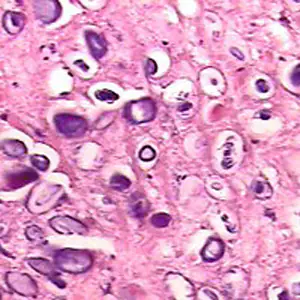

Microscopic identification of eggs and proglottids in feces is diagnostic for taeniasis, but is not possible during the first 3 months following infection, prior to development of adult tapeworms. Repeated examination and concentration techniques will increase the likelihood of detecting light infections. Nevertheless, identification of Taenia is not possible if solely based on microscopic examination of eggs, because all Taenia species produce eggs that are morphologically identical. Eggs of Taenia spp. are also indistinguishable from those produced by cestodes of the genus Echinococcus (tapeworms of dogs and other canid hosts). Microscopic identification of gravid proglottids (or, more rarely, examination of the scolex) allows species determination.

Separation of T. saginata and T. solium is best accomplished by examination of mature proglottids. Taenia saginata has 12-30 primary lateral uterine branches, while T. solium has 7-13 primary lateral uterine branches. Visualization of the branches can be improved by clearing the specimen in lactophenol followed by India ink injection into the lateral genital pore. The procedure is as follows: